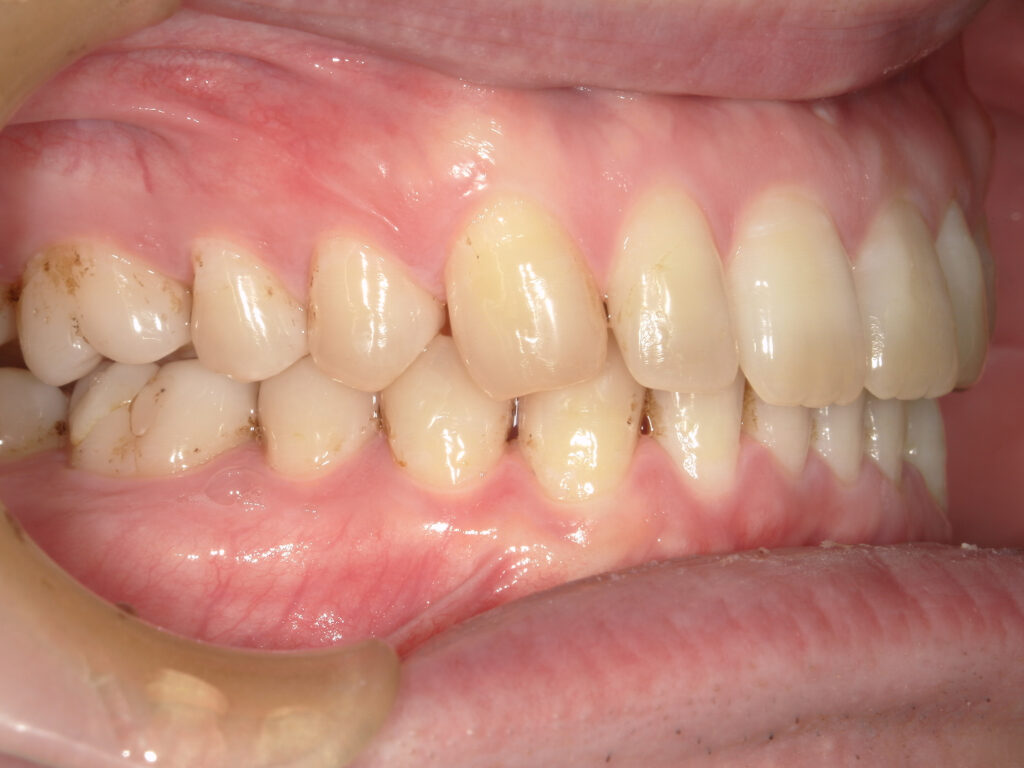

左側

治療後

患者様は上下の横の前歯の隙間を気にされており、「できれば完全に隙間を閉じたいが、ある程度改善されればよい」とのご希望で来院された。 インビザライン矯正では、前歯の近接移動を中心に計画し、効率的に隙間を閉鎖するため犬歯・小臼歯にアタッチメントを付与。また、閉鎖後の歯肉退縮やブラックトライアングルを最小限に抑えるため、歯根の平行性を意識して移動を行った。 治療により上下前歯の隙間は良好に閉鎖し、咬合も安定。審美的な改善とともに、発音や清掃性の向上にもつながった。 |